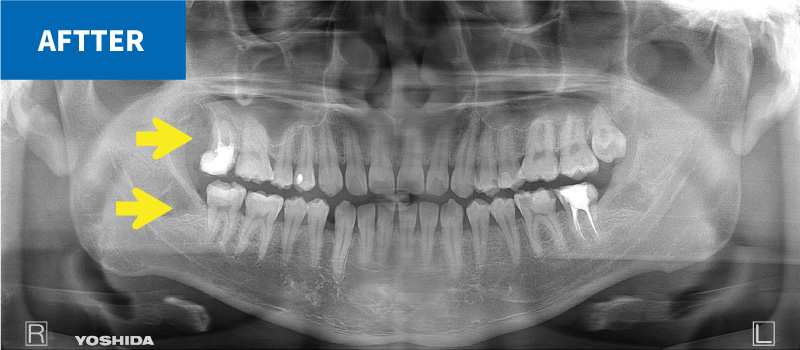

一般歯科診療では敬遠されがちな、重要神経管(下歯槽神経管:下顎の神経と動脈・静脈が入っている管)に接する親知らず

抜く方向や角度を十分にシミュレーションして安全抜歯を心がけている。

上の親知らずには、歯並びと逸脱した方向に生えてしまうものが多くあります。

これらは、咬み合わせに悪影響を及ぼすだけでなく、周囲の歯の虫歯や歯周病の原因となってしまうことがあります。

これらを安全に抜歯することも口腔外科の仕事です。